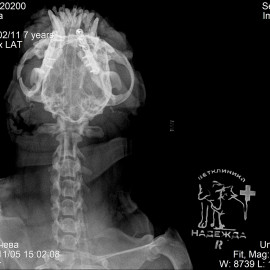

В другой клинике был поставлен диагноз: перелом тела нижней челюсти правой и левой стороны. Была проведена операция: остеосинтез нижней челюсти.

Снимок 1-2 до операции.